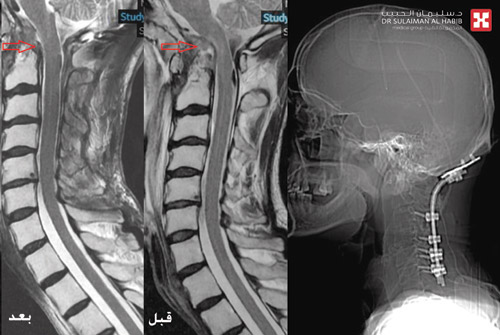

وبعد دراسة الحالة وضع الفريق الطبي خطة علاجية تبدأ بمعالجة الالتهابات بالدم والفقرات العنقية، وتركيب أنبوبين أحدهما لتصريف السائل الشوكي الدماغي لمعالجة مشكلة الاستسقاء، وآخر خارجي بالمعدة للقيام بمهمة التغذية. وبعد ذلك خضع المريض لعملية معقدة استغرقت 6 ساعات تحت التخدير العام وباستخدام جهاز المراقبة العصبية، وتم فيها تثبيت أربع فقرات عنقية مع قاعدة الجمجمة الخلفية وتوسيع الحجرة الخلفية للدماغ، وإزالة جزء من الفقرة الأطلسية.

وأكد د. محسن أن جهود الفريق الطبي تكللت بالنجاح ولله الحمد ونقل المريض لجناح التنويم وأبانت الأشعة استقرار حالته الصحية، وتم إزالة أنبوب التغذية الخارجي لأن المريض استعاد القدرة على الأكل والشرب، كما انتهت لدى المريض مشكلة فقرات الرقبة والاستسقاء الدماغي بصورة نهائية، وتم معالجة كافة الالتهابات بالعظم والدم والصدر. وقد غادر المريض المستشفى بعد 5 أيام وهو بحالة صحية مستقرة، مع وضع برنامج متابعة بالعيادة لمدة شهرين لاستكمال التأهيل العلاجي.